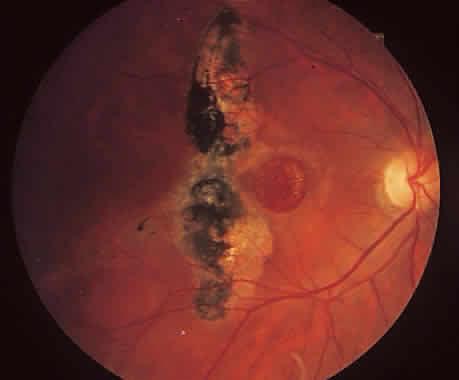

SUBMACULAR SURGERY. Because laser photocoagulation of subfoveal CNV results in loss of central vision and is associated with a high rate of recurrence, the Submacular Surgery Trials were initiated to study whether removal of subfoveal CNV could alter the known history. This study has several arms that address new subfoveal CNV, subfoveal CNV associated with histoplasmosis or idiopathic, and submacular hemorrhage related to AMD. Long-term follow-up has found that AMD-related CNV treated with submacular surgery can result in better-than-expected stable vision. Nevertheless, damage to the RPE leads to loss of photoreceptors and choriocapillaris that ultimately degrades vision (Fig. 14).97

Fig. 14. A. Large choroidal neovascularization complex is noted with subretinal hemorrhage and fluid. B. The patient underwent submacular surgery with removal of the choroidal neovascularization complex. Note loss of retinal pigment epithelium in area of membrane and hemorrhage. C. Three months after surgery, the choriocapillaris has atrophied and choroidal vessels are better visualized.